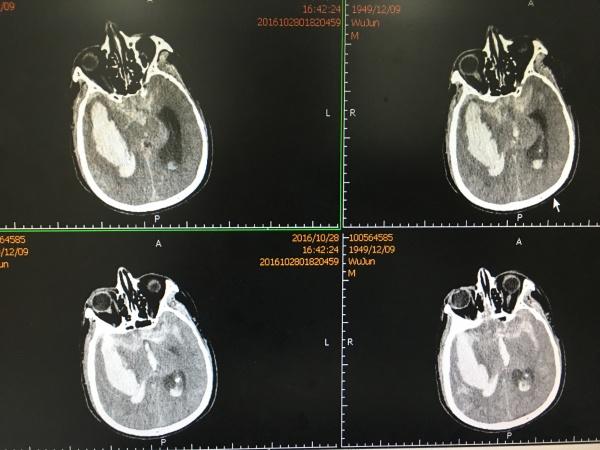

见MCA供血区大面积梗塞,查凝血无明显异常,予以改善微循环、扩容等对症治疗,1周后再次复查CT:

CT所见MCA供血区梗塞明显好转,骨窗处见硬膜下积液,此时患者评分改善,刺痛可睁眼,有摸索动作。

再过一周,再次复查CT示: